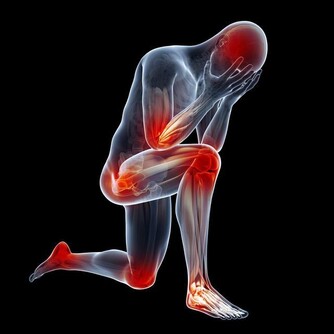

人體膝關節的使用壽命一般有60年,而且膝關節的損耗是無法修復的,如何延長膝關節的使用壽命呢?

膝關節壽命只有60年,磨損不可修復

關節的壽命是有限的。一旦關節“氣數已盡”,就會引發各種關節病!關節的壽命主要是由基因決定的,一般的健康壽命是60年。

想必大家都聽過“樹老根先枯,人老腿先衰”,現在不僅僅是老年人經常出現膝蓋酸痛,很多的年輕人也會時不時出現膝蓋疼痛,這是因為什麼呢?

膝蓋不是身體中最常受傷的部位,卻是最薄弱、要求最高的關節,原因是它們經常承受的人的整個重量,而且由於活動範圍大,其結構使它們比髖關節和踝關節更在衝擊下更脆弱。